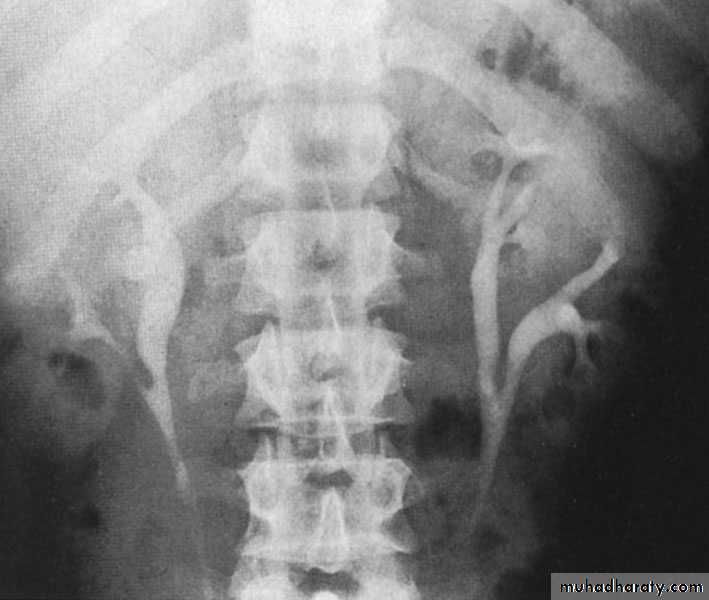

Duplication of the ureter

Incidence : 3 %Usually the ureters fuse & have common orifice in the bladder although they may open independently in which case the ureters cross each other so that the ureter that drain the upper pelvis open below (more distally) in the bladder & vise versa.

Ureteral duplication: partial and complete

Partial duplication: is more common. Two ureters draining single kidney for variable length, then unite together before entering the bladder in one ureteric orifice. Rarely the lower part is duplicated as inverted Y ureter.Complete duplication:

Less frequent, the whole ureter is duplicated, and each one opens in separate orifice in the bladder. The ureter draining the upper partopens more distally

in the bladder.

Bifid renal pelvis

iComplete ureteral duplication and ectopic ureteric orifice.